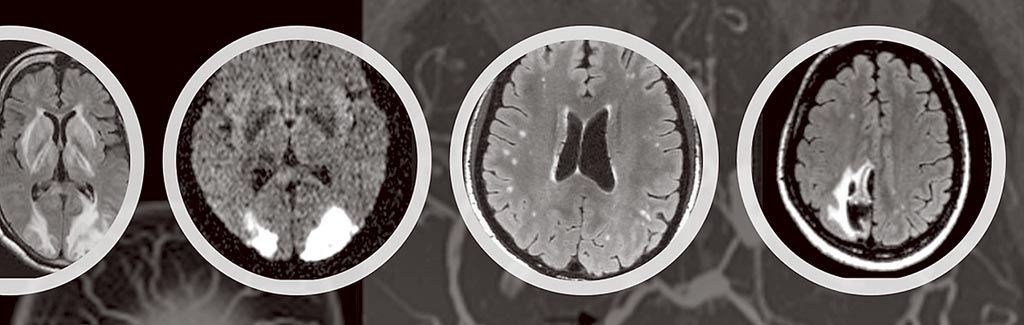

可逆性腦血管收縮症候群 華人健康網

經常頭痛 小心 可逆性腦血管收縮症候群 龔晉賢診所健康園地 痞客邦

救援雷擊頭痛新技術解析腦部特徵 生活新聞 中國時報